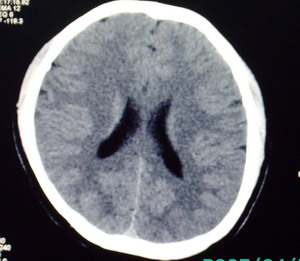

以下是引用九目段在2007-12-24 14:55:00的发言:[br]1,年轻女性[br]2,ct表现:左侧脑室三角区可见一不规则小明显强化的结节,中央见小低密度,侧脑室无扩张。[br]分析:[br]常见的有三种肿瘤好发三角区:[br]1,脉络丛乳头状瘤,好发于年轻者,明显强化,实性,分泌脑脊液,常伴有侧脑室扩大,肿瘤较小可以脑室扩大不明显,不能排除,但小结节尚不易形成坏死腔。[br]2,室管膜瘤,好发于儿童及青少年,明显强化,易坏死,大时伴脑室扩张。[br]3,脑膜瘤,明显强化,圆形,界请,无脑积水,一般不坏死。[br]诊断:[br]左侧脑室三角区结节,考虑室管膜瘤可能性大,不排除脉络丛乳头状瘤和脑膜瘤(因病史较长)。[br][br][本贴已被 九目段 于 2007-12-24 15:13:35 修改过]